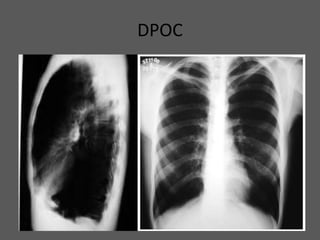

DPOC